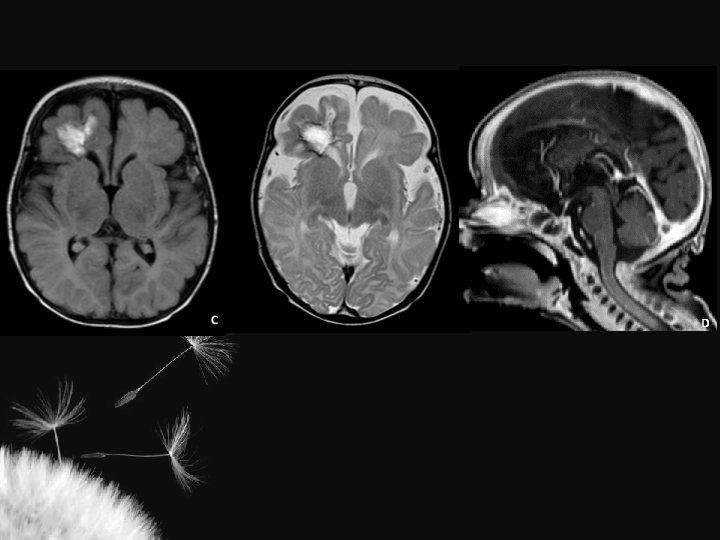

LESÃO HIPÓXICO-ISQUÊMICA NO RN TERMO